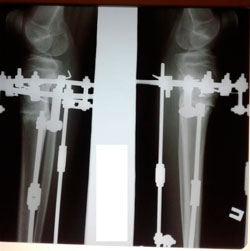

Исходник - 13 лет.

Диагноз: варусная деформация голеней + Ротация с обеих сторон.

Дата операции - 30.06.2020